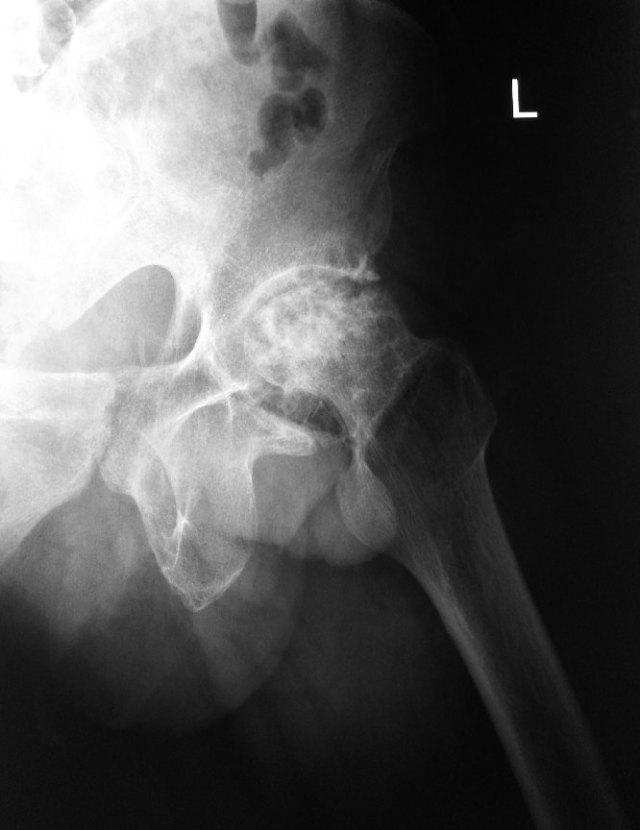

He presented with pain in his hip a year later. X-rays showed severe osteoarthritis of his left hip due to AVN.

He eventually agreed to undergo a left total hip replacement surgery.

A left total hip replacement was done.